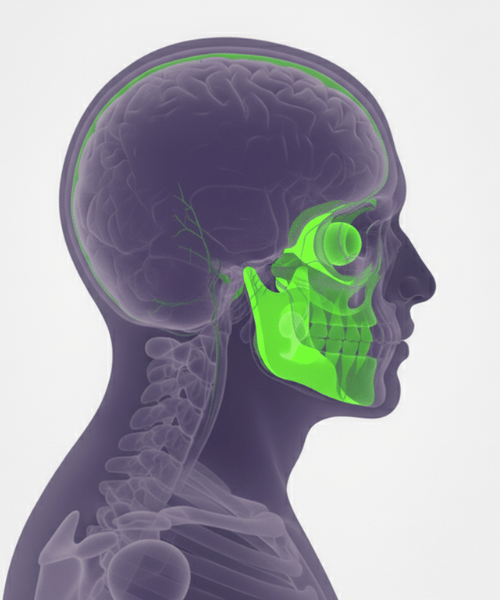

Comprehensive MRI examination of the temporomandibular joint to diagnose jaw pain, clicking, and movement disorders with precision.